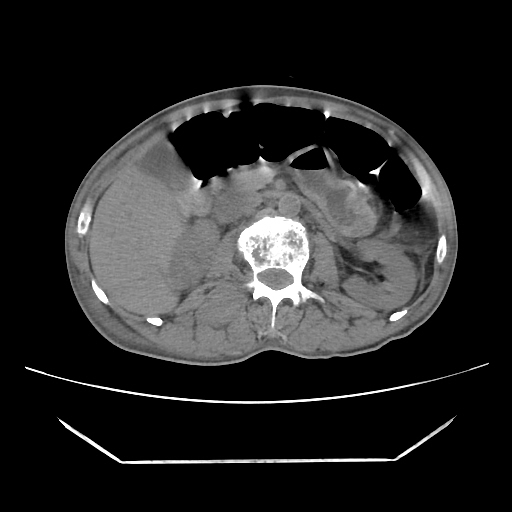

A 56 years old man with

HRCT done on summer season starting 2016